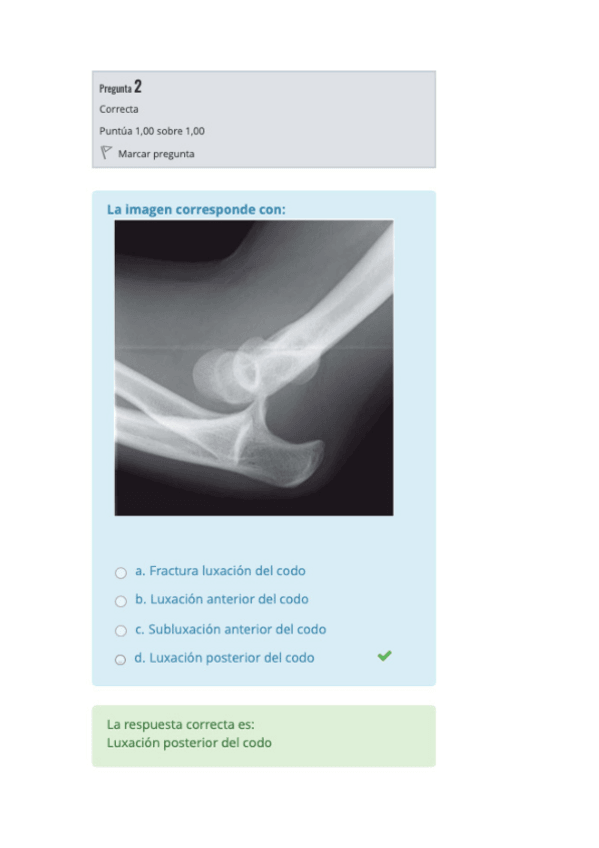

He publicado nuevos apuntes de 2º Radiologia General: SEGUNDO-PARCIAL-RADIOLOGIA-2021.pdf